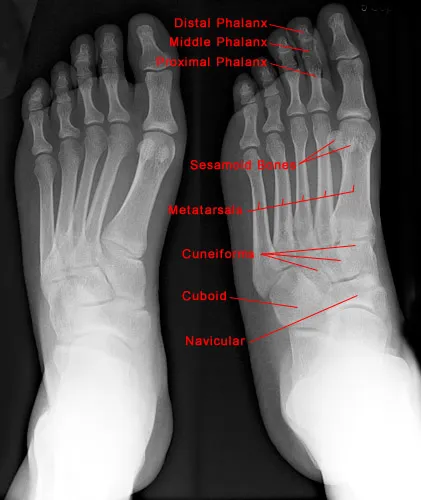

Foot Fractures - Bones & Breaks 101

- Hindfoot: Talus (connects to tibia/fibula), Calcaneus (heel bone).

- Midfoot: Navicular, Cuboid, 3 Cuneiforms. Forms arches.

- Forefoot: 5 Metatarsals (MT), 14 Phalanges.